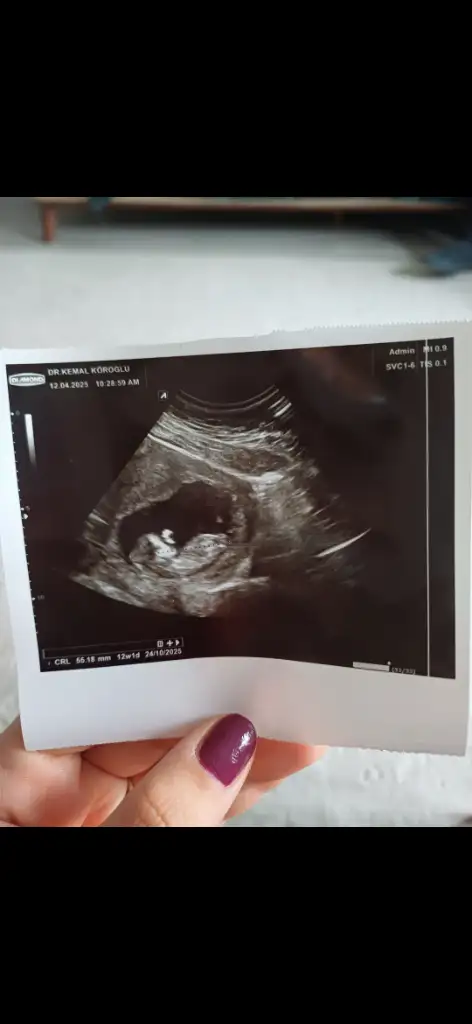

Merhaba ilk önce rabbim hayırlısını ve gönlünüze göre olanı versin inşallah nub teoremine göre sanki kız gibiEki Görüntüle 3580977 cinsiyet tahmini alabilir miyim

Yaa bizede bakabilir misiniz çok merak ediyorum görsellerde ilk görsel 10+4 diğer görseller 6+4 haftalık :)Pek iyi anlamıyorum ama nub teorisi fotolarına baktığım kadarıyla kız gibi görünüyor

Banada bakabilir miisniz görsel olarak yorumlara ekledim :)Merhaba ilk önce rabbim hayırlısını ve gönlünüze göre olanı versin inşallah nub teoremine göre sanki kız gibi

Banada bakabilir miisniz görsel olarak yorumlara ekledim :) ilk görsel 10+4 diğer görseller 6+4 haftalıkken karından ultrasonla bakıldı

Pek anlamıyorum ama kendim için araştırmaya girdim kaç gündür araştırmalarıma göre kız gibi geldi banaBana da tahminde bulunabilir misiniz kızlar 10. Hafta goruntumden

Merhaba nub teoremine gore kiza benzettim ben ama rabbim go lunuze gore versin insallahBana da tahminde bulunabilir misiniz kızlar 10. Hafta goruntumden